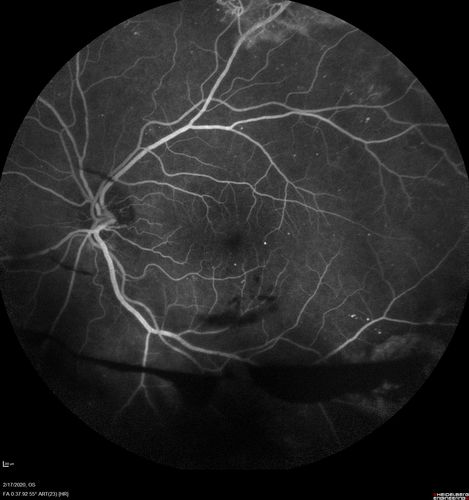

PDR and Vitreous Hemorrhage - High Risk Left Eye - Low Risk Right Eye

50 year old man with type I diabetes mellitus for 26 years. New Vitreous Hemorrhage in the left eye. Both eyes have NVE. Both also have foveal hypoplasia